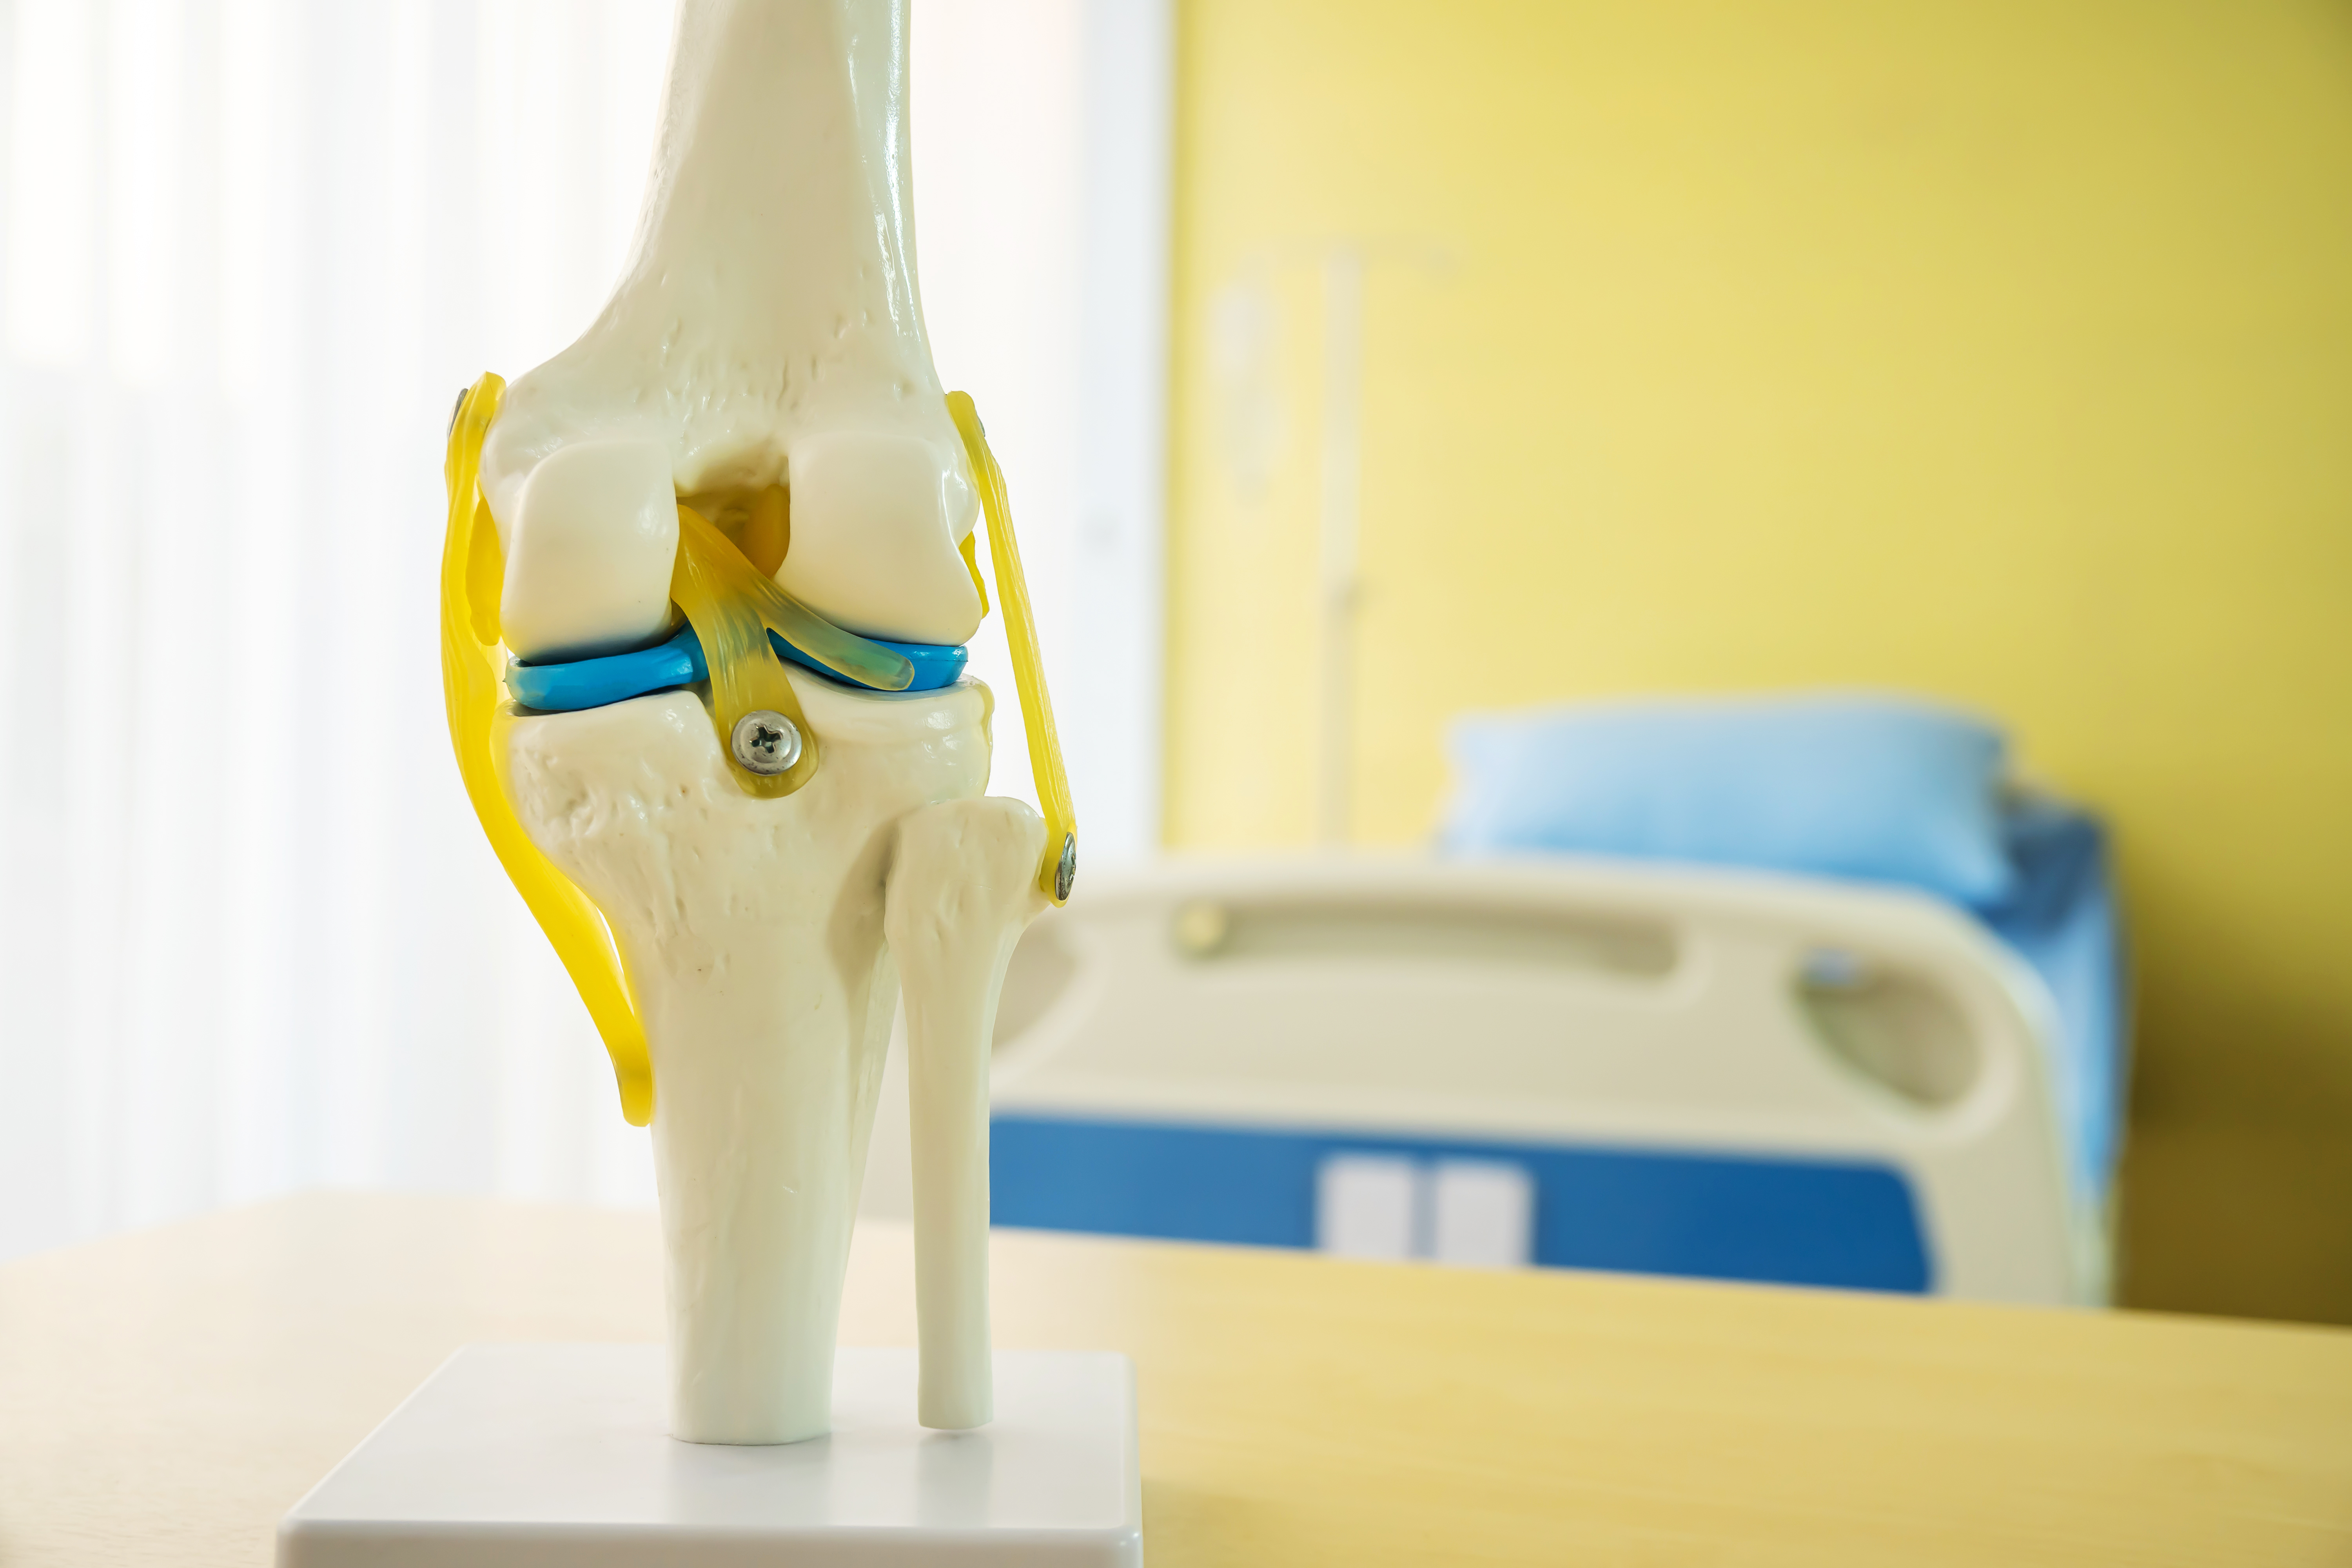

Menisküs nedir?

Menisküs, diz ekleminde femur (uyluk kemiği) ve tibia (kaval kemiği) arasındaki boşluğu kaplayan ve yastıklayan bir yapıdır. Her dizde iki menisküs vardır - biri içeride (medial menisküs) ve diğeri dışarıda (lateral menisküs).

Her biri güçlü fibrokartilajdan yapılmıştır ve hilal veya "C" harfi şeklindedir. Bu menisküsler, femur ve kaval kemiğinin eklem yüzeylerinin şekline dikkatlice kalıplanmış vantuzlara benziyor.

Menisküsün şekli ve boyutu, çeşitli işlevlere hizmet etmesine izin verir. Ayağa kalktığınızda, ağırlığınız eşit şekilde bacaklarınızdan dizlerinize kadar taşınır. Yürürken, koşarken ve zıplarken bu ağırlığın diz üzerindeki baskısı daha da artar. Menisküs, diz eklemindeki kemiklerin birbirine sürtünerek hasara neden olmasını engelleyen bir yastık görevi görür. Ayrıca ağırlığınızın yükünü diz eklemi boyunca eşit olarak iletir. Bu yük paylaşımı, diz yaralanmalarını önlemeye yardımcı olur ve dizin işlevi ve sağlığı için son derece önemlidir.